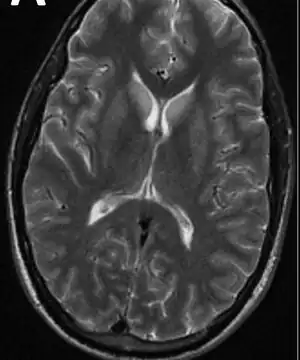

Neuroimaging and lumbar puncture (LP) are both essential methods of diagnosing viral encephalitis. Computed tomography (CT) or magnetic resonance imaging (MRI) help identify increased intracranial pressure and the risk of uncal herniation before performing an LP. Cerebrospinal fluid (CSF), if analyzed, should be analyzed for opening pressure, cell counts, glucose, protein, and IgG and IgM antibodies. CSF testing should also include polymerase chain reaction (PCR) testing for herpes simplex viruses 1 and 2 and enteroviruses. About 10% of patients have normal CSF results. Additional testing, such as serology for various arboviruses and HIV testing, may also be performed based on the individual's history and symptoms. Brain biopsy and body fluid specimen cultures and PCR may also be useful in some cases. Electroencephalography (EEG) is abnormal in more than 80% of viral encephalitis cases, including those who are experiencing seizures, and may need to be monitored continuously to identify non-convulsive status. Lack of testing resources may prevent accurate diagnosis.[1][5]

- For herpes simplex virus encephalitis, a CT scan may show low-density lesions in the temporal lobe. These lesions usually appear 3 to 5 days after the start of the infection.